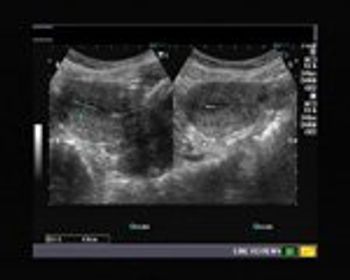

This is an ultrasound scan of the pelvis in 35 year old female patient.

Using only this image, describe what phase of the menstrual cycle this patient is in.